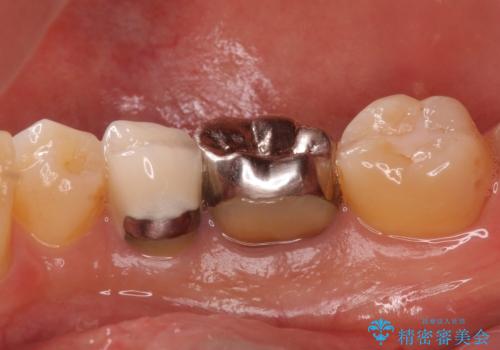

- 口を開けたときに下の歯の銀歯が目立つから白くしたいとのことで来院されました。

根管治療はご希望されなかったため、被せ物のみをやり替えていきます。

- 右下6 仮歯+ジルコニアクラウン 11,000円+121,000円費用は治療当時の料金となります